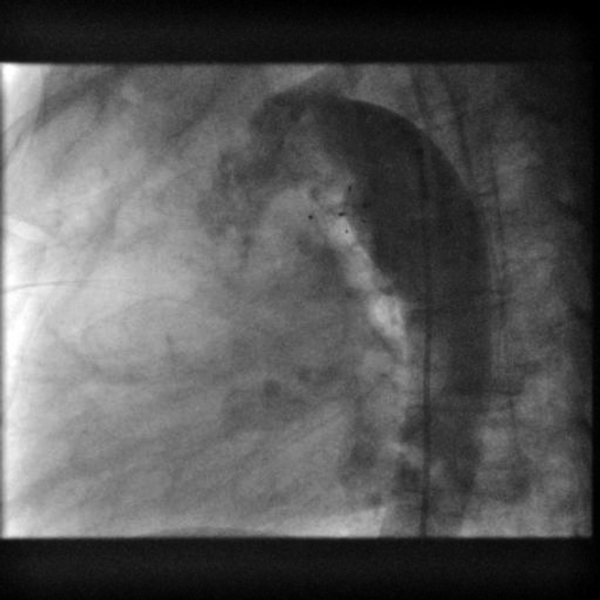

左→右短絡によるQp/Qsは1.2と推定され,心臓カテーテル検査の方針となった.身長168.6 cm,体重71.8 kg,血圧120/66 mmHg,脈拍数76回/分,経皮的酸素飽和度97%,浮腫なし,心拍整,第二肋間胸骨左縁Levine I/VI continuous murmur, bounding pulseなし,呼吸音清,腹部平坦軟,肝脾触知しない.入院時の胸部X線では心胸郭比(CTR : cardio thoracic ratio)47%と心拡大は軽度で,肺血管陰影の増強を認めなかった(Fig. 1).12誘導心電図は洞調律で心拍数60回/分,QRS軸-30°,有意な異常所見は認めなかった(Fig. 2).血液検査では,白血球9,700/µL, AST 28 U/L, ALT 36 U/L, NT-proBNP< 10 pg/mL, LDH 206 U/L, CPK 86 U/Lであった(Table 1).心エコー検査では肺動脈内連続性短絡血流があり(Fig. 3),収縮期max vel=3.7 m/sec拡張期max vel=2.9 m/secであった.また,軽度の僧帽弁逆流を認めた.左室駆出分画73%,左室流入波形(E/A=2.2 E/E′=6.9)と左室機能は保たれていた.明らかな下行大動脈の拡張期逆行性血流は認めなかった.心臓カテーテル検査では,下行大動脈からの造影でPDAはKrichenko A型(Fig. 4)に描出され,ampulla径3.5 mm, PA側2.2 mm,最狭部2.5 mm,長さ8.9 mmであった.Fick法を用いて計算したQp/Qsは1.0,肺血管抵抗値は1.08 Wood単位・m2であった.成人先天性心疾患診療ガイドライン4)に基づき,推奨クラスI,エビデンスレベルCと判断し,初回治療後34年目に再閉鎖目的で入院となった.

Fig. 1 Chest X-ray on admission

Cardiothoracic ratio was 47% without pulmonary congestion.